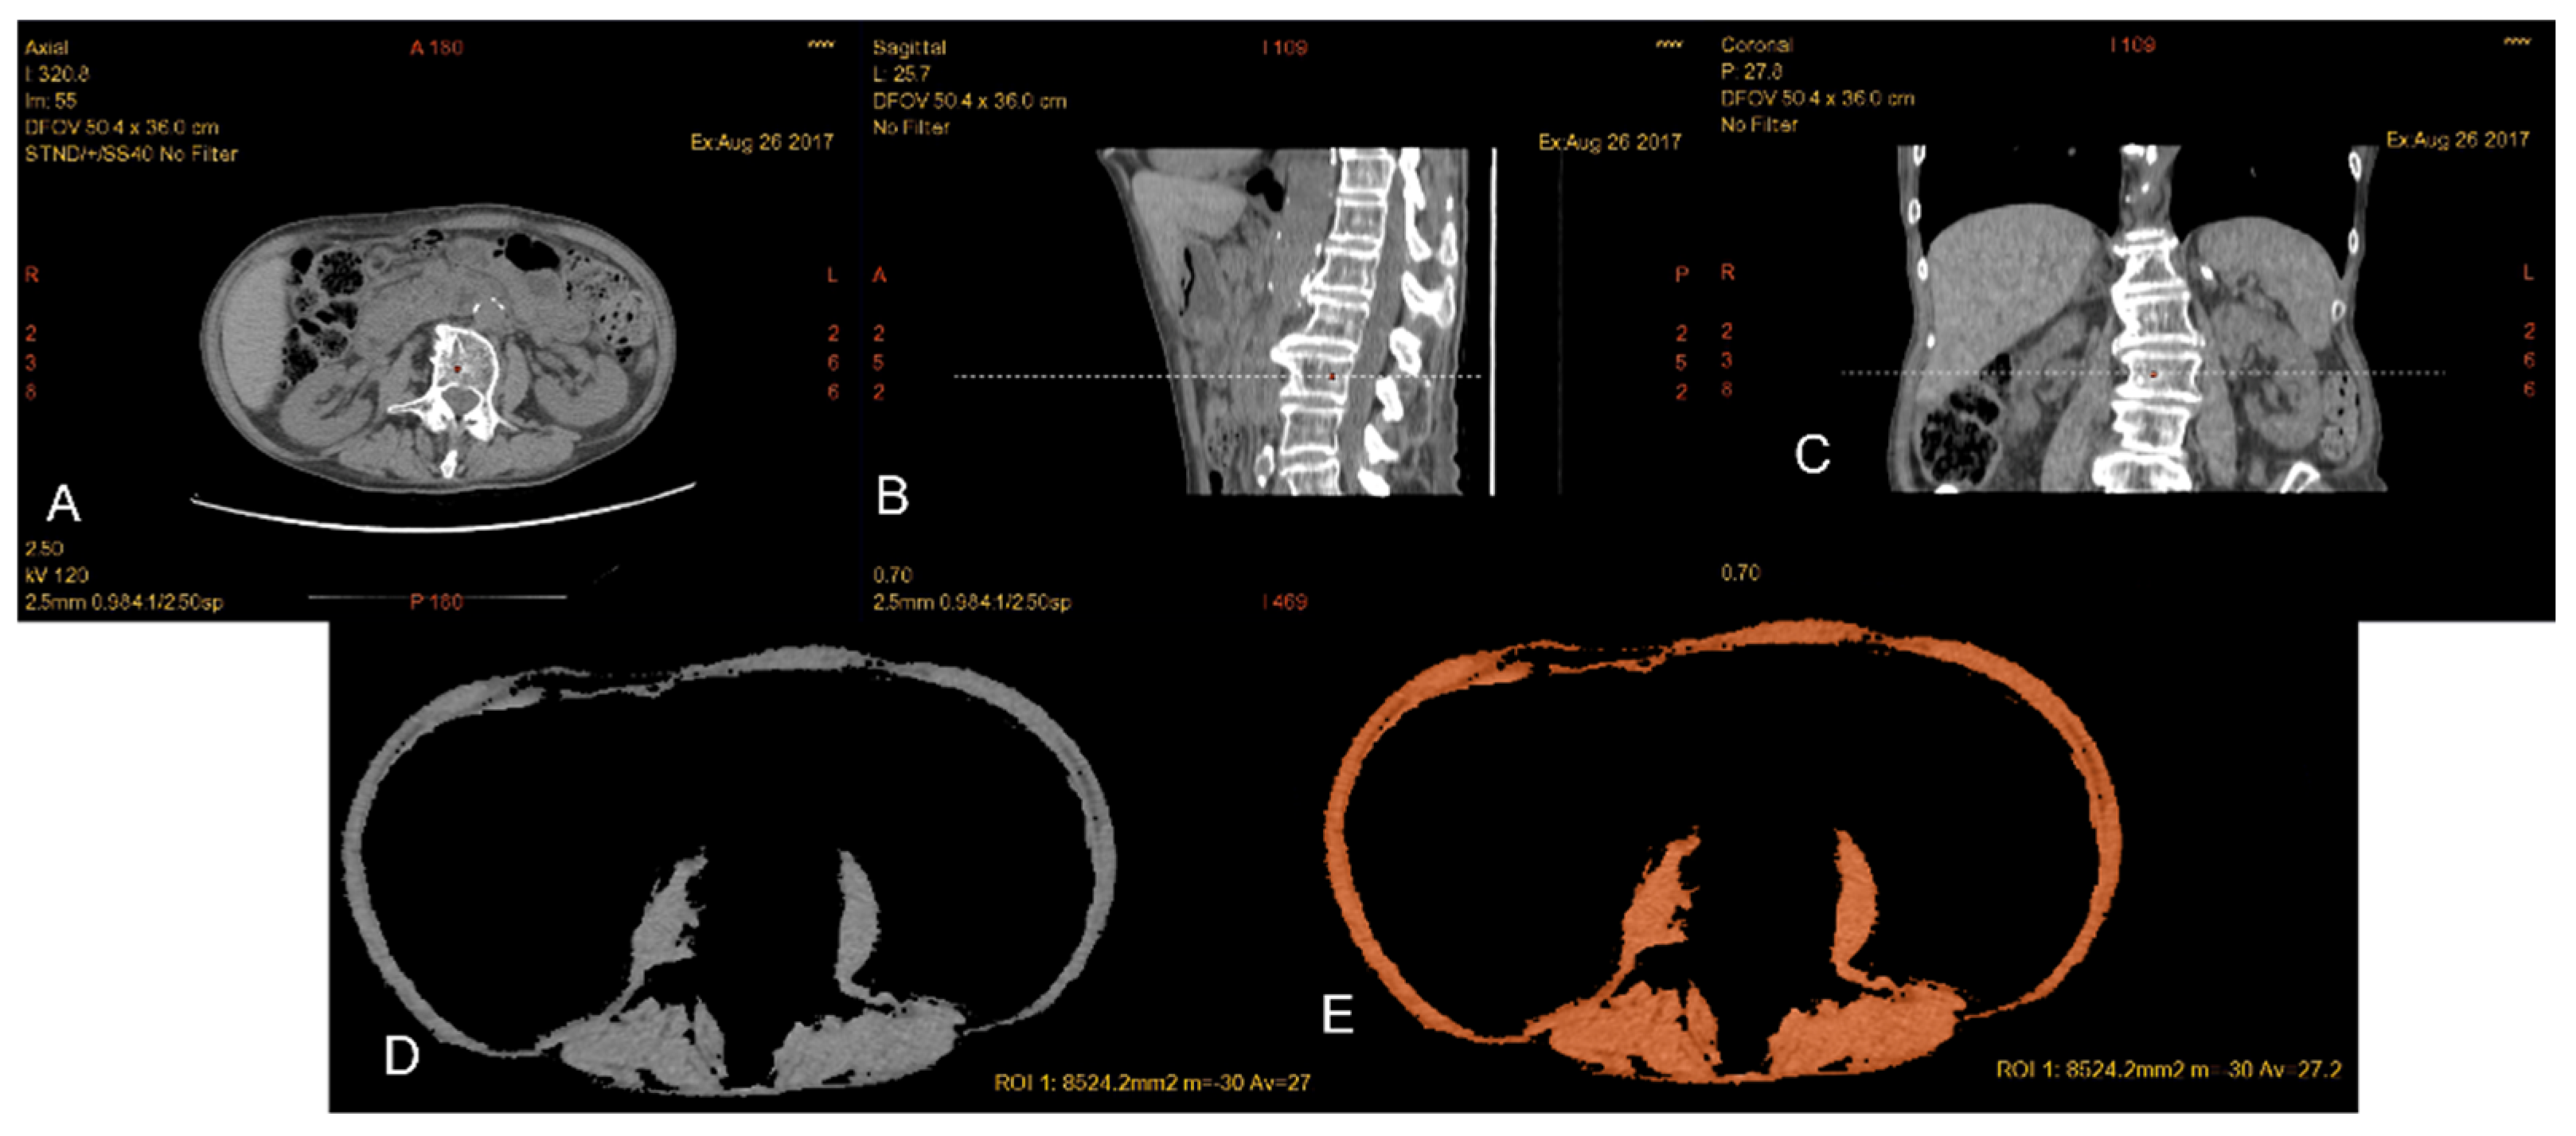

2.1. Muscle Mass Measurement